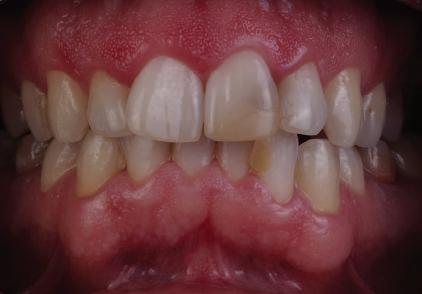

Пациентът постъпи в клиниката с молба за тотална рехабилитация на усмивката. Той не харесваше централ ните си резци, които според него бяха твърде къси и квадратни. Имаше раз стояние от медиално и дистално на латералните му резци. Друго сериоз но оплакване бе свързано с металоке рамичната корона на зъб 12, която бе жълтеникава и неестетична, като цяло не харесваше вида на венците си и както самият той се изразяваше, „вижда се прекалено много от венците при усмивка“.

След диагностиката бяха направени екстра- и интраорални снимки, както и рентгенографии; професионалното почистване бе от изключителна важ ност, бяха дадени и инструкции за лич на орална хигиена. Бе направено интра орално сканиране с Medit i500. Цялата тази информация бе използ вана в приложението Smilecloud за 2D биометричен дизайн. В приложението са налични естест вени форми на зъбите и щом бяха под брани зъби и бе направен дизайн

библиотеката на Exocad. Струва си да се отбележи, че 2D дизайнът от Smile Cloud бе спазен до последния детайл в Exocad smile creator с цел да се създаде 3D obj файл със зъбните форми. След като естетичният дизайн бе готов в model creator модула на Exocad, адитивен 3D мок-ъп модел бе експорти ран и принтиран от принтер Formlabs 3. Моделът бе използван за направата на силиконов водач, за да се изготви мо тивационен мок-ъп в устата на паци ента и да се оценят естетичните па раметри. След като пациентът одобри вида на усмивката си, мок-ъпът бе използван за финализиране дизайна на усмивка та. Мок-ъпът бе използван също така като водач по време на мекотъканна та хирургия, както и при препарация на зъбите.

Препарираните зъби бяха импорти рани в Exocad и насложени върху ес тествените форми от биометричния дизайн, като така стана ясно дали зъ бите са били препарирани коректно. По този начин зъболекарят и зъботехни кът работят в една и съща екосистема и резултатът е оптимален. С короната се справихме чрез диги тална редукция на циркония в Exocad, като по този начин на практика създа дохме циркониево кепе, след което про изведохме фасета от IPS Empress Cad Multi. Кепето от Katana Zirconia на зъб 12 с букално послойно нанесена керами ка бе фрезовано (послойното нанасяне бе направено, за да се подобри връзката и да се осигури адхезивно циментиране на фасетата към циркониевото кепе, както и за да се напасне цветът към този на съседните зъби). При първото сканиране регистрирах ме цялата горна зъбна дъга, така че, ко гато се наложи да сканираме повторно, бе изтрит и сканиран наново само зъб 12, тъй като венците не бяха отдръп нати при второто сканиране.

Една седмица след препарацията на зъбите и циментирането на цирко ниевото кепе бяха изработени 12 IPS Empress Cad Multi фасети. Макро- и микротекстурата на фасе тите бяха направени на ръка, след кое то бяха нанесени 3D характеризации с боички, а полирането отново бе напра вено ръчно, за да им се придаде естест вен и естетичен вид. Предизвикателството тук беше короната да има същите оптични характеристики като тези на остана лите зъби при естествена светлина, през поляризационен и флуоресцентен филтър. 3D принтерът бе Fromlabs, софтуерът за фрезоване – Mill Box, а фрез апаратът –imes icore CORiTEC 350i. В крайна сметка постигнахме ес тествен вид на усмивката с натурал на зъбна морфология при изцяло диги тален протокол, при който дизайнът бе направен първоначално и през всич ки етапи на лечението се придържахме към него до самия край Излишно е да отбелязваме, че всички сме удовлетворени от постигнатото! Преди След Победител в категория „Клиничен случай с изцяло дигитален протокол“ в конкурса „Усмивка на годината 2022“

11Dental Tribune Bulgarian Edition / октомври 2022 г. Преди лечението Фиг. 1 Фиг. 2 Фиг. 3 Фиг. 4 Фиг. 5 Фиг. 6 Фиг. 7 Фиг. 9 Фиг. 10 Фиг. 11 Фиг. 8 Фиг. 12 Фиг. 13

12 Dental Tribune Bulgarian Edition / октомври 2022 г. По време на лечението Фиг. 14 Фиг. 16 Фиг. 20 Фиг. 23 Фиг. 21 Фиг. 24 Фиг. 26 Фиг. 28 Фиг. 31 Фиг. 34 Фиг. 29 Фиг. 32 Фиг. 35 Фиг. 30 Фиг. 33 Фиг. 36 Фиг. 27 Фиг. 22 Фиг. 25 Фиг. 17 Фиг. 18 Фиг. 19 Фиг. 15

13Dental Tribune Bulgarian Edition / октомври 2022 г. След лечението За авторите: Д-р Калин Маринов е специалист в областта на имплантологията, протетиката и естетичната хирургия. Завършил е дентална медици на в София през 2012 г. През 2014 г. основава Sky Dental Clinic. Бил е на обмен ни начала в катедра „Протетика“ на Университета по дентална медицина във Фрайбург, Германия. Живял е и е практикувал в Мелбърн, Австралия, и е посеща вал курсове и лекции в Италия, Швейцария, Германия с насоченост в естетич ната хирургия и имплантология, както и тоталната рехабилитация на устна та кухина чрез импланти. Зт. Стефан Петров основава собствена лаборатория през 2006 г. Официален демонстратор на GC за България, като от 2015 г. е KOL за Източна Европа. Инструктор е на Straumann за България. Лаборатория та му има сертификат за пилотна лаборатория на Micerium – Италия. Носител е на множество награди в денталния конкурс „Усмивка на годината”. Носител е на награда CERAMISTS MASTER CUP с д-р Софиен Риахи в престижния международен конгрес CERAMISTS – NO LIMITS 2015 г. Изнася лекции и провежда курсове в редица европейски страни. Фиг. 37 Фиг. 40 Фиг. 43 Фиг. 45 Фиг. 47 Фиг. 50 Фиг. 48 Фиг. 49 Фиг. 41 Фиг. 44 Фиг. 46 Фиг. 42 Фиг. 38 Фиг. 39